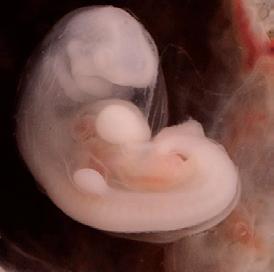

2nd Month: 5–8 Weeks

By six weeks, brain waves can be detected.3 The jaw forms, including teeth and taste buds.4 The baby begins to swallow amniotic fluid, and sometimes hiccups.5 Fingers and toes are developing and at seven weeks the chest and abdomen are fully formed.6 Swimming in the amniotic fluid, she now looks like a miniature human infant.7,8